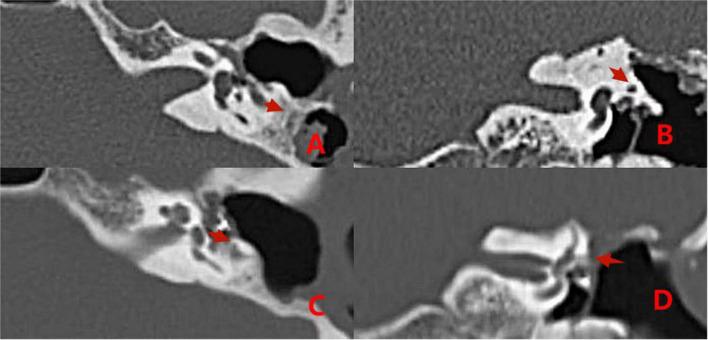

In group 1, from January 2008 to December 2014, 29 patients with middle ear cholesteatoma complicated by labyrinthine fistulas were treated with surgery involving covering the fistulas with simple fascia. In group 2, from January 2015 to October 2021, 36 patients with middle ear cholesteatoma complicated by labyrinthine fistulas were included. Cholesteatomas on the surface of type I labyrinthine fistulas were cleaned using the "under water technique" and capped with a "sandwich" composed of fascia, bone meal, and fascia. Cholesteatomas on the surface of type II and III fistulas were cleaned using the "under water technique," and the labyrinthine fistula was plugged with a "pie" composed of fascia, bone meal, and fascia, and then covered with bone wax.

Some patients with labyrinthine fistulas in group 1 exhibited symptoms of vertigo after surgery. In group 2 Patients with type II labyrinthine fistulas experienced short-term vertigo after semicircular canal occlusion, but no cases of vertigo were reported during long-term follow-up. "sandwich." In patients with type II labyrinthine fistulas, the semicircular canal occlusion influenced postoperative hearing improvement. However, postoperative patient hearing was still superior to preoperative hearing.

The surface of type I labyrinthine fistulas should be capped by a "sandwich" composed of fascia, bone meal, and fascia. Type II and III labyrinthine fistulas should be plugged with a "pie" composed of fascia, bone meal, and fascia, covered with bone wax.